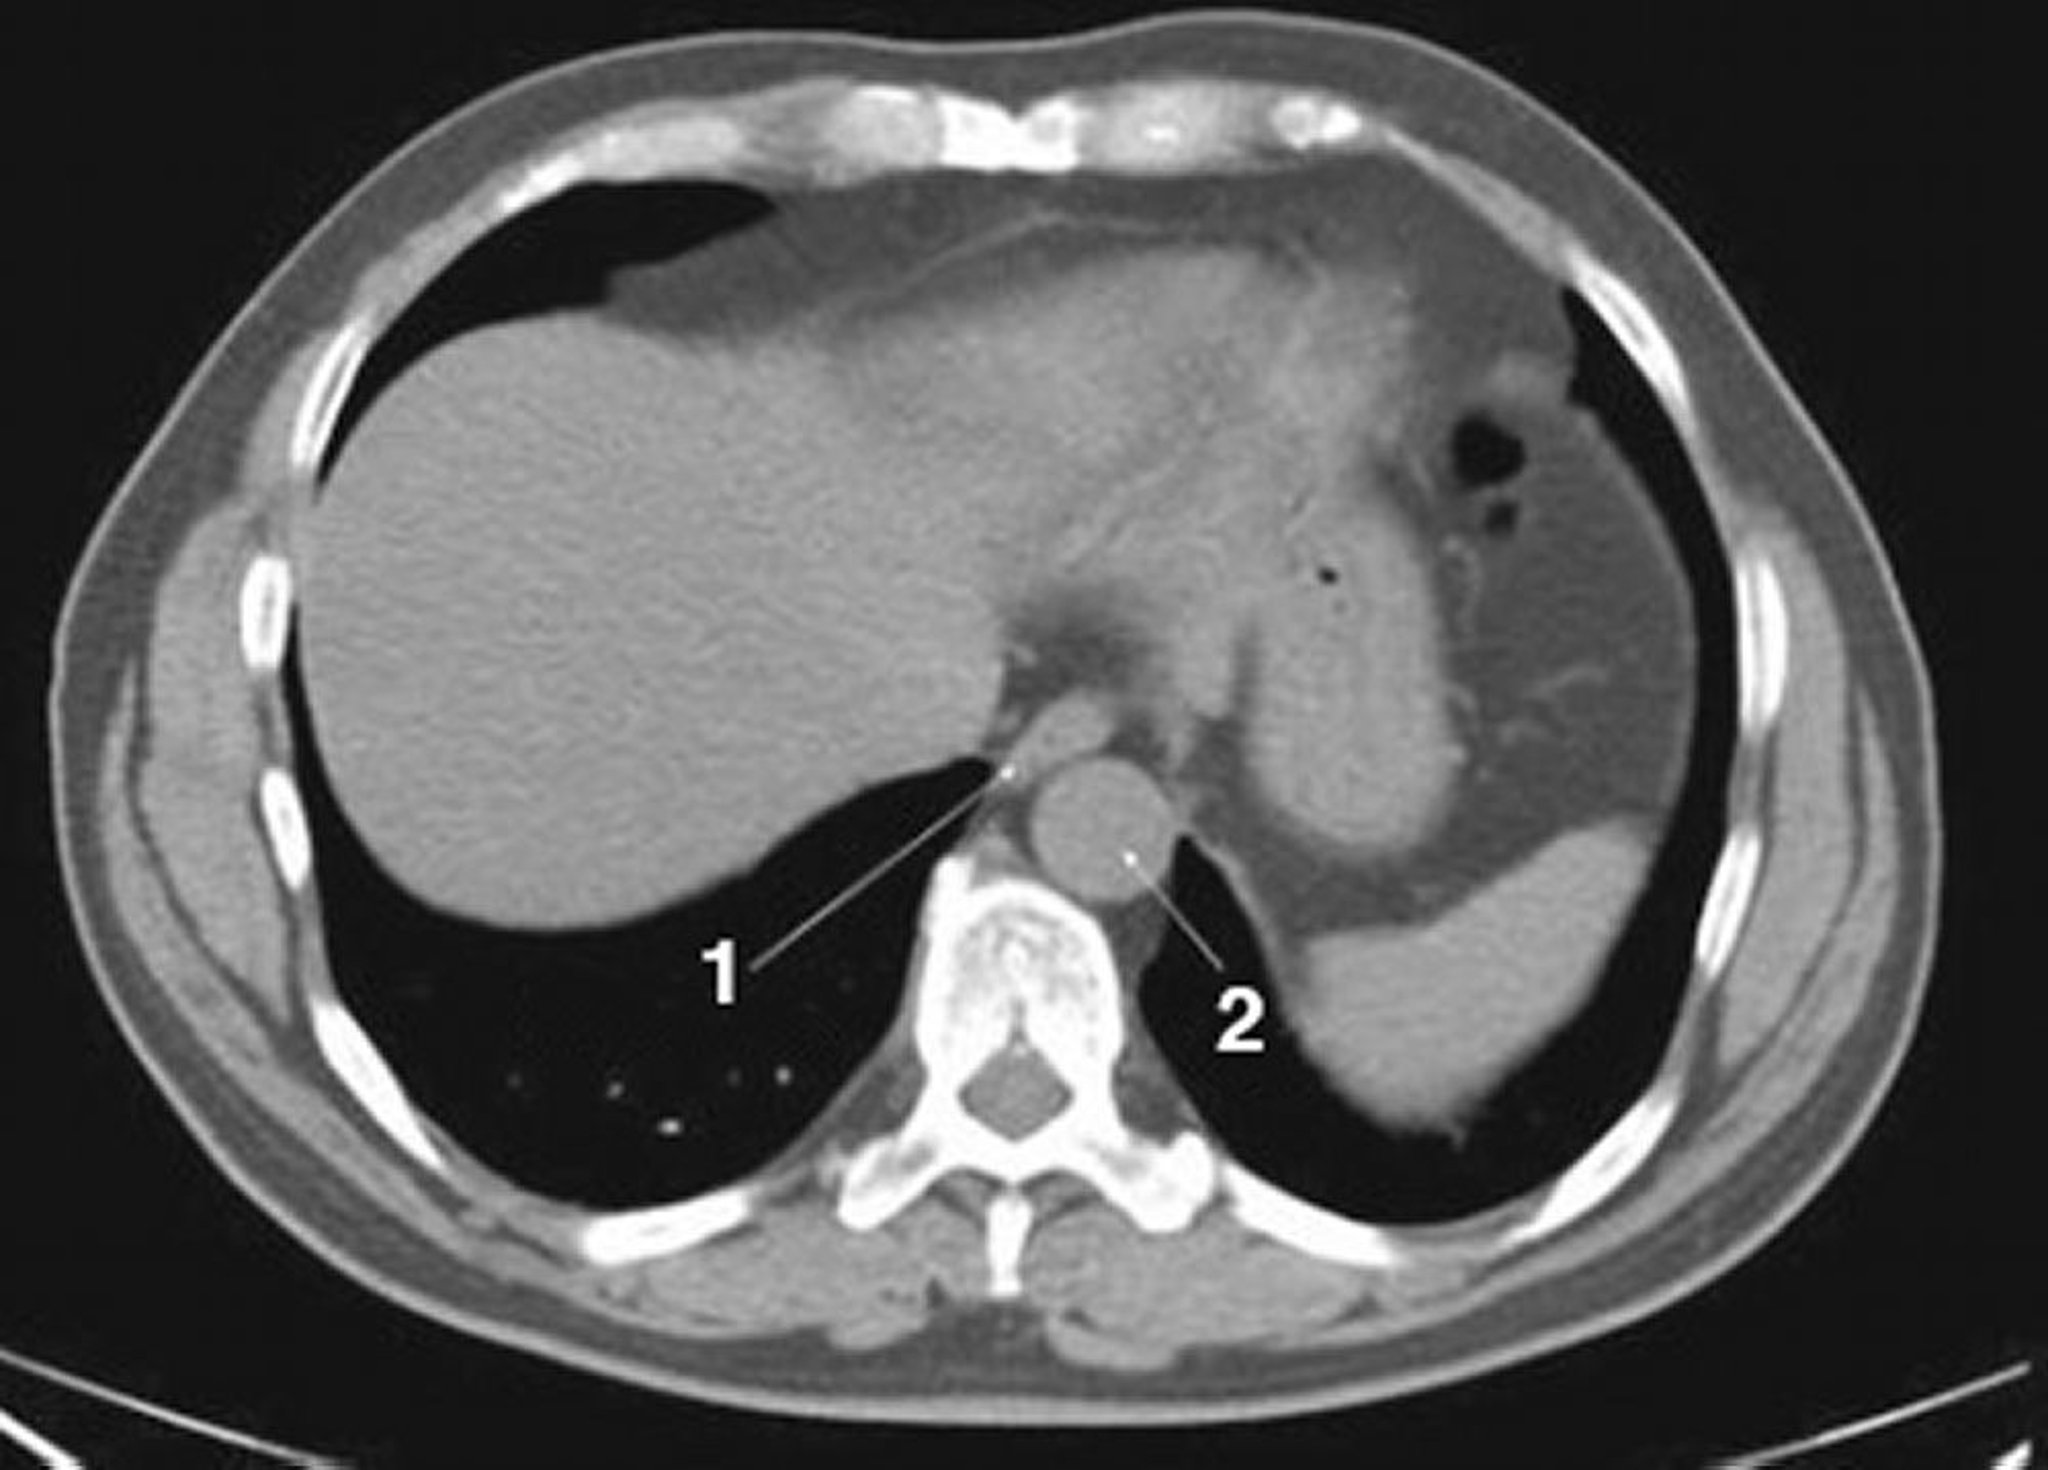

TDM sans contraste de l'abdomen et du bassin montrant une anatomie normale (diapositive 1)

1 = œsophage; 2 = aorte.